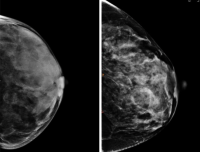

Same density, different patterns and cancer risk. As seen with mammography, breasts with the same density can have different texture patterns (seen above). In a new study, patterns of breast tissue apparent on mammograms and quantified by computer analysis were a better predicter of breast cancer risk than breast density. Images provided by Despina Kontos.

A new study now suggests that six different breast texture patterns, also seen in mammograms, can do a better job at predicting which women will develop breast cancer in the future.

Smaller, earlier studies suggested that differences in texture—patterns in the way fat and glandular tissue is distributed in the breast—may also be related to breast cancer risk.

“Different patterns are visible to radiologists who examine mammography images—some look clumpy, some look smooth, some look more spotty,” Kontos says. “But beyond making a determination of overall density, radiologists had no way to quantify these patterns and turn them into data needed to determine their link to cancer risk.”

“Given that women with the same breast density can have substantially different texture patterns, our analysis provides important additional information for estimating breast cancer risk,” Kontos says.